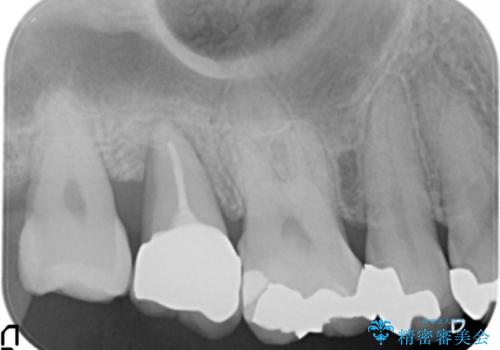

「状態の悪い銀歯がなくなりすっきりした」と喜んで下さいました。

見た目や使用感にご満足頂き、他の部位も現在治療中です。

クラウンの種類:オールセラミッククラウン ベレッツァ